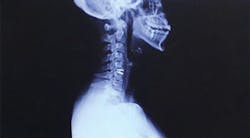

A herniated disk was the cause of years of pain resulting from improper workplace ergonomics

While it did take some time, a neurologist finally confirmed that a herniated disk in my neck was the cause of my pain. I was initially prescribed one month of physical therapy, which eventually turned into three. The co-pays and the unpaid sick time I needed to take away from the office added up to approximately $5,000. Unfortunately, physical therapy was only a short-term fix, and the herniated disk continued to wreak havoc on my life.